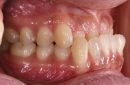

Dientes ectópicos

Estos dientes requieren auxiliares especiales, extracciones y condiciones periodontales adecuadas para poder manejarlos correctamente.